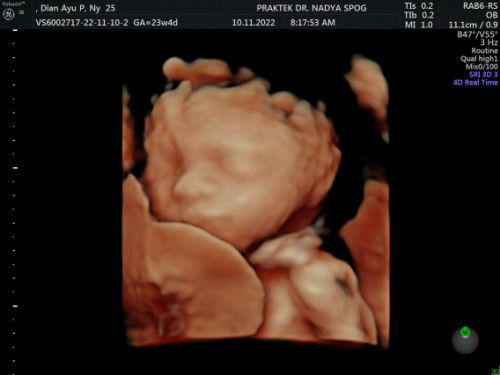

Bun, mau cerita saya lagi hamil anak pertama usia kandungan 23w4d. Tadi pagi saya usg, ternyata saat usg terlihat kalo tali pusarnya melilit di leher. Jujur saya khawatir😭 saat periksa dokter bilang ddjnya 145 bpm, masih normal. Saya tanya dokter bagaimana caranya supaya ga terlilit tali pusar, dokter bilang ngga ada cara apapun karna itu bisa terjadi akibat pergerakan dari janin. Minta doanya ya bun, semoga ini tidak membahayakan. Semoga pergerakan janinnya bisa melepas lilitan dan tidak terjadi lilitan lagi dikemudian hari. Semoga janin saya sehat dan selamat sampai kami dipertemukan nanti dengan keadaan yg sehat, normal dan sempurna. Aamiin🤲🏻#firstmom #firstbaby